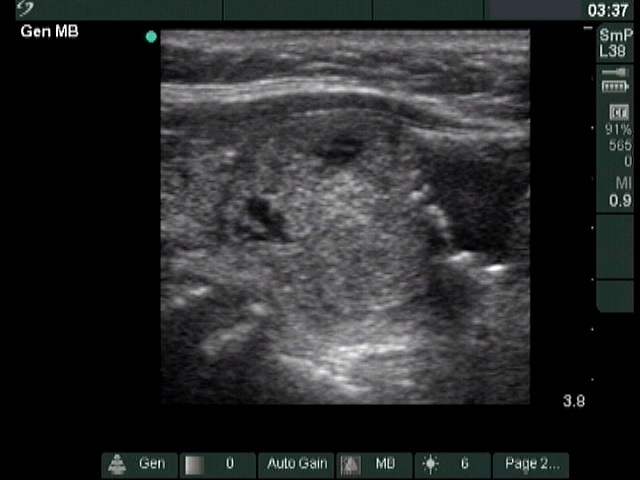

Second examination 7 years later (second and third rows of images):

Clinical presentation: The patient remained euthyroid in the previous years an had no complaints.

Result of blood test: TSH 0.34 mIU/L, FT4 14.2 pM/L

Ultrasonography. The presentation remained unchanged. Using a better ultrasound device, it turned out that the echogenic granules are related to ventral cystic areas. Therefore, these are not microcalcifications, but figures caused by back wall cystic enhancement.Suggestion: yearly TSH determination, ultrasound in 4 years.